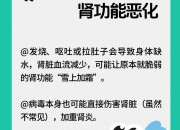

对于肾脏,大家可能是既熟悉又陌生,它是人体的重要器官,负责过滤血液中的废物、调节水分和电解质平衡、维持血压和产生红细胞等。慢性肾病(CKD)是全球重要的公共卫生问题,影响超过8.5亿人,数据表明,预计到2040年,慢性肾病将成为全球导致预期寿命缩短的第五大病因。慢性肾病早期往往没有明显症状,因此容易被忽视,当肾脏功能严重受损时,可能会导致肾衰竭,甚至需要透析或肾移植来维持生命。根据中国医师协会肾脏